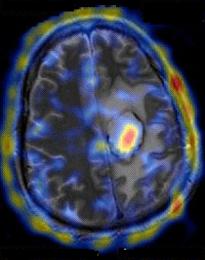

Extrem de sofisticate sunt echipamentele PET (positron emission tomography), ce utilizeaza radioizotopi ce emit pozitroni. O imagine tomografica a creierului este prezentata in Figura 4, iar in Figura 5 este prezentat un tomograf.

|

Figura 4 |